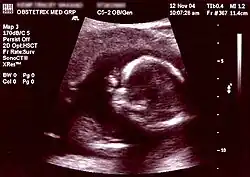

![]() An example of an algorithm for prenatal testing for chromosomal abnormalities.[1] | |